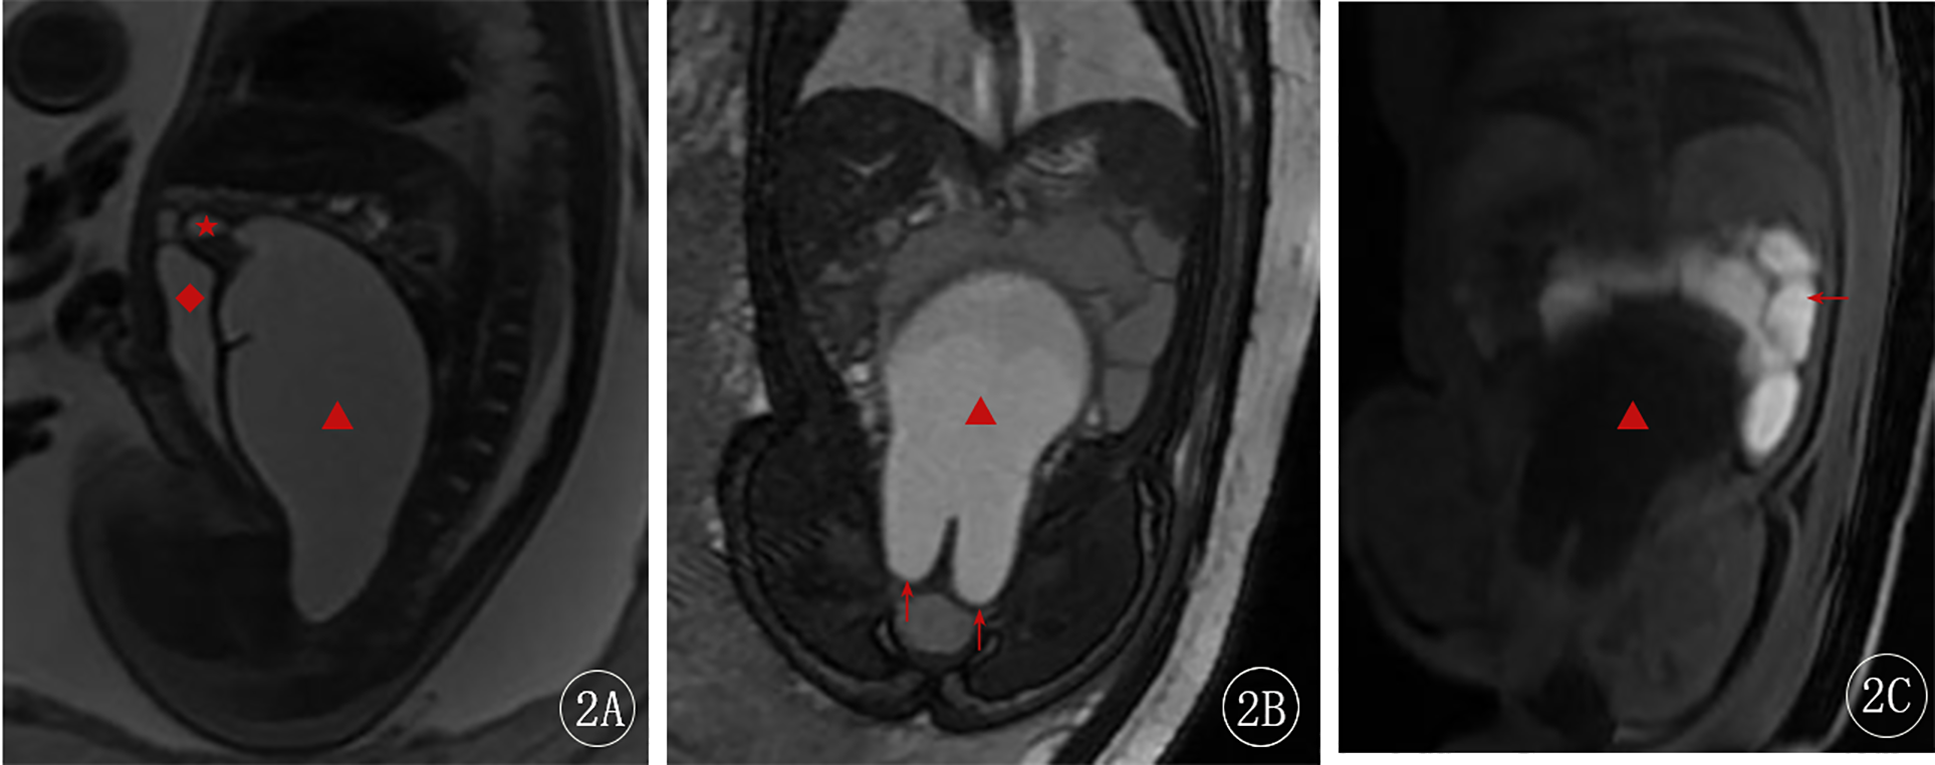

The ultrasound diagnosis was fetal bladder enlargement with an associated abdominal cystic mass. At 37 weeks + 6 days, a fetal MRI was performed, which showed a cystic structure measuring approximately 100 mm × 50 mm × 57 mm posterior to the fetal bladder. The cyst had low signal on T1-weighted images and high signal on T2-weighted images, with heterogeneous internal signal. The inferior margin of the cyst showed a “reverse rabbit ear” sign. A uterus-like structure was connected to the superior aspect of the cyst, with a small amount of fluid within its cavity, measuring approximately 10 mm × 6 mm. Compression of the adjacent bowel and bladder was noted (Figure 2). The fetal MRI diagnosis was a fetal abdominal cystic structure, most likely representing an imperforate hymen with associated voluminous vaginal and uterine fluid collection, as well as localized vaginal septation or adhesions in the superior and inferior aspects of the vagina.

Figure 2

Fetal MRI at 37 weeks + 6 days. (A) Sagittal 2D FIESTA image—the red star (★) indicates the uterine cavity, and the red diamond (◆) shows the compressed bladder. (B) Coronal 2D FIESTA image—the red arrow points to the distal vaginal obstruction, showing the “reverse rabbit ear” sign. (C) Coronal LAVA-Flex image—the red arrow indicates the compressed bowel.

Fetal MRI, with its high resolution and ability to image in multiple planes and angles, is not affected by maternal or fetal positioning, and provides superior delineation of the detailed anatomy of the vagina and uterus for the diagnosis of imperforate hymen (7). In the present case, the fetal ultrasound was unable to clearly differentiate the bladder from the lesion, but the fetal abdominal MRI clearly visualized the dilated vagina and uterus, the distal vaginal obstruction (“reverse rabbit ear” sign), and the detailed anatomy of the uterus and vagina, providing a definitive diagnosis and guiding the treatment strategy.